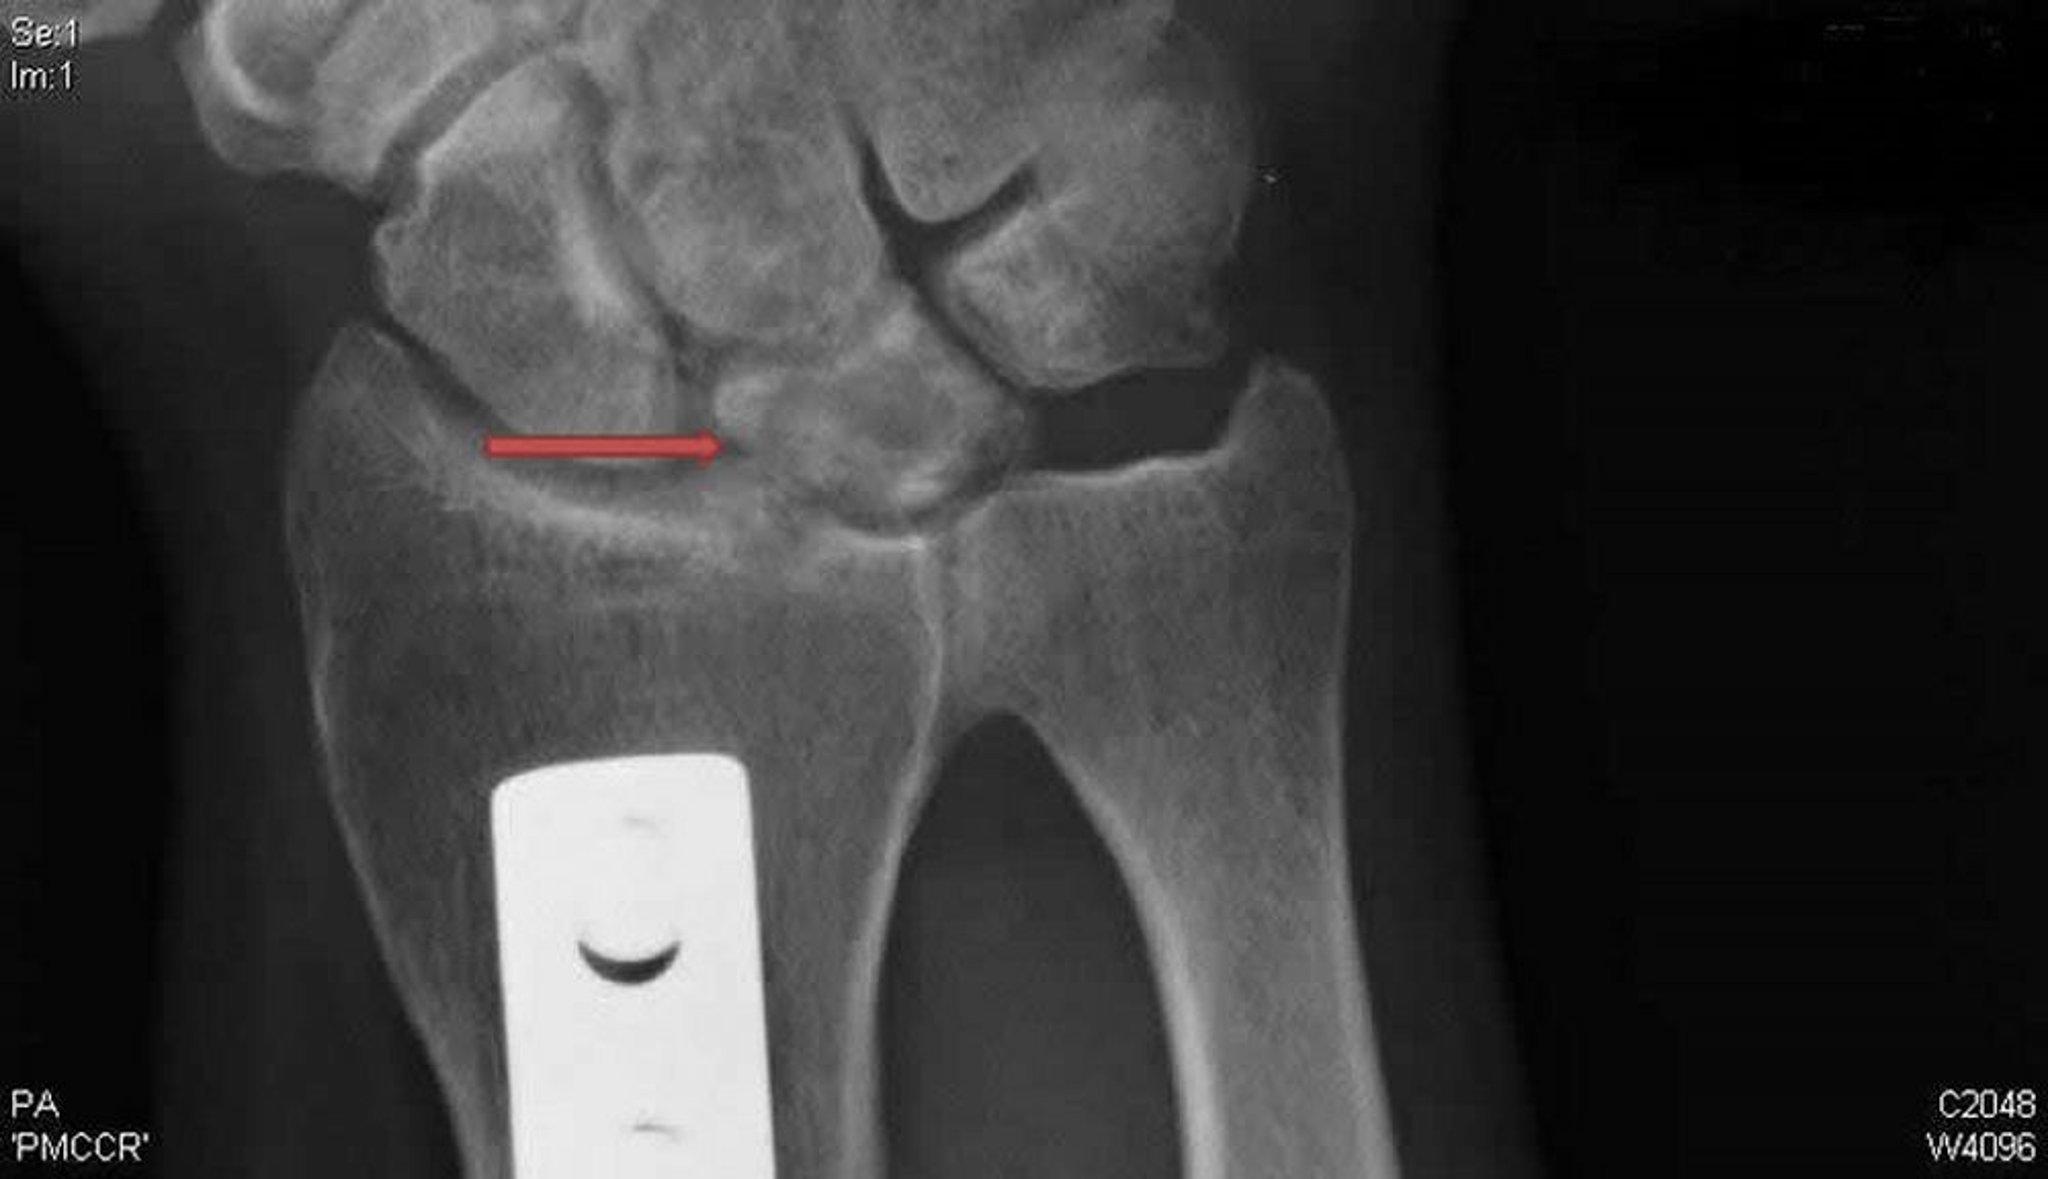

Doença de Kienböck (radiografia em incidência posteroanterior)

Essa radiografia posteroanterior do punho direito mostra cistos e esclerose do osso lunar (seta) típicos da doença de Kienböck. A placa de metal é evidência de uma osteotomia de encurtamento radial feita na tentativa de liberar o semilunar e potencialmente tratar essa doença.

Radiografia, cortesia de David R. Steinberg, MD.